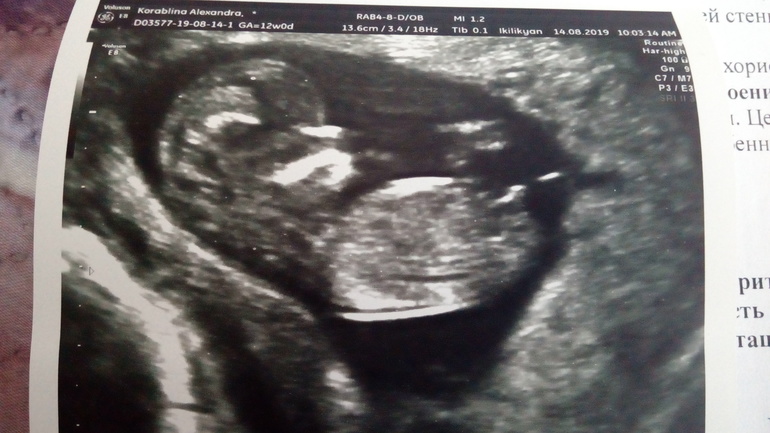

Похож на мальчиковый бугорок)) сама сижу гадаю! Посмотрите кого видите у меня?))

У вас похоже девочка 😊 но я тоже не эксперт, только вот по такой картинке знаю можно определять) угол